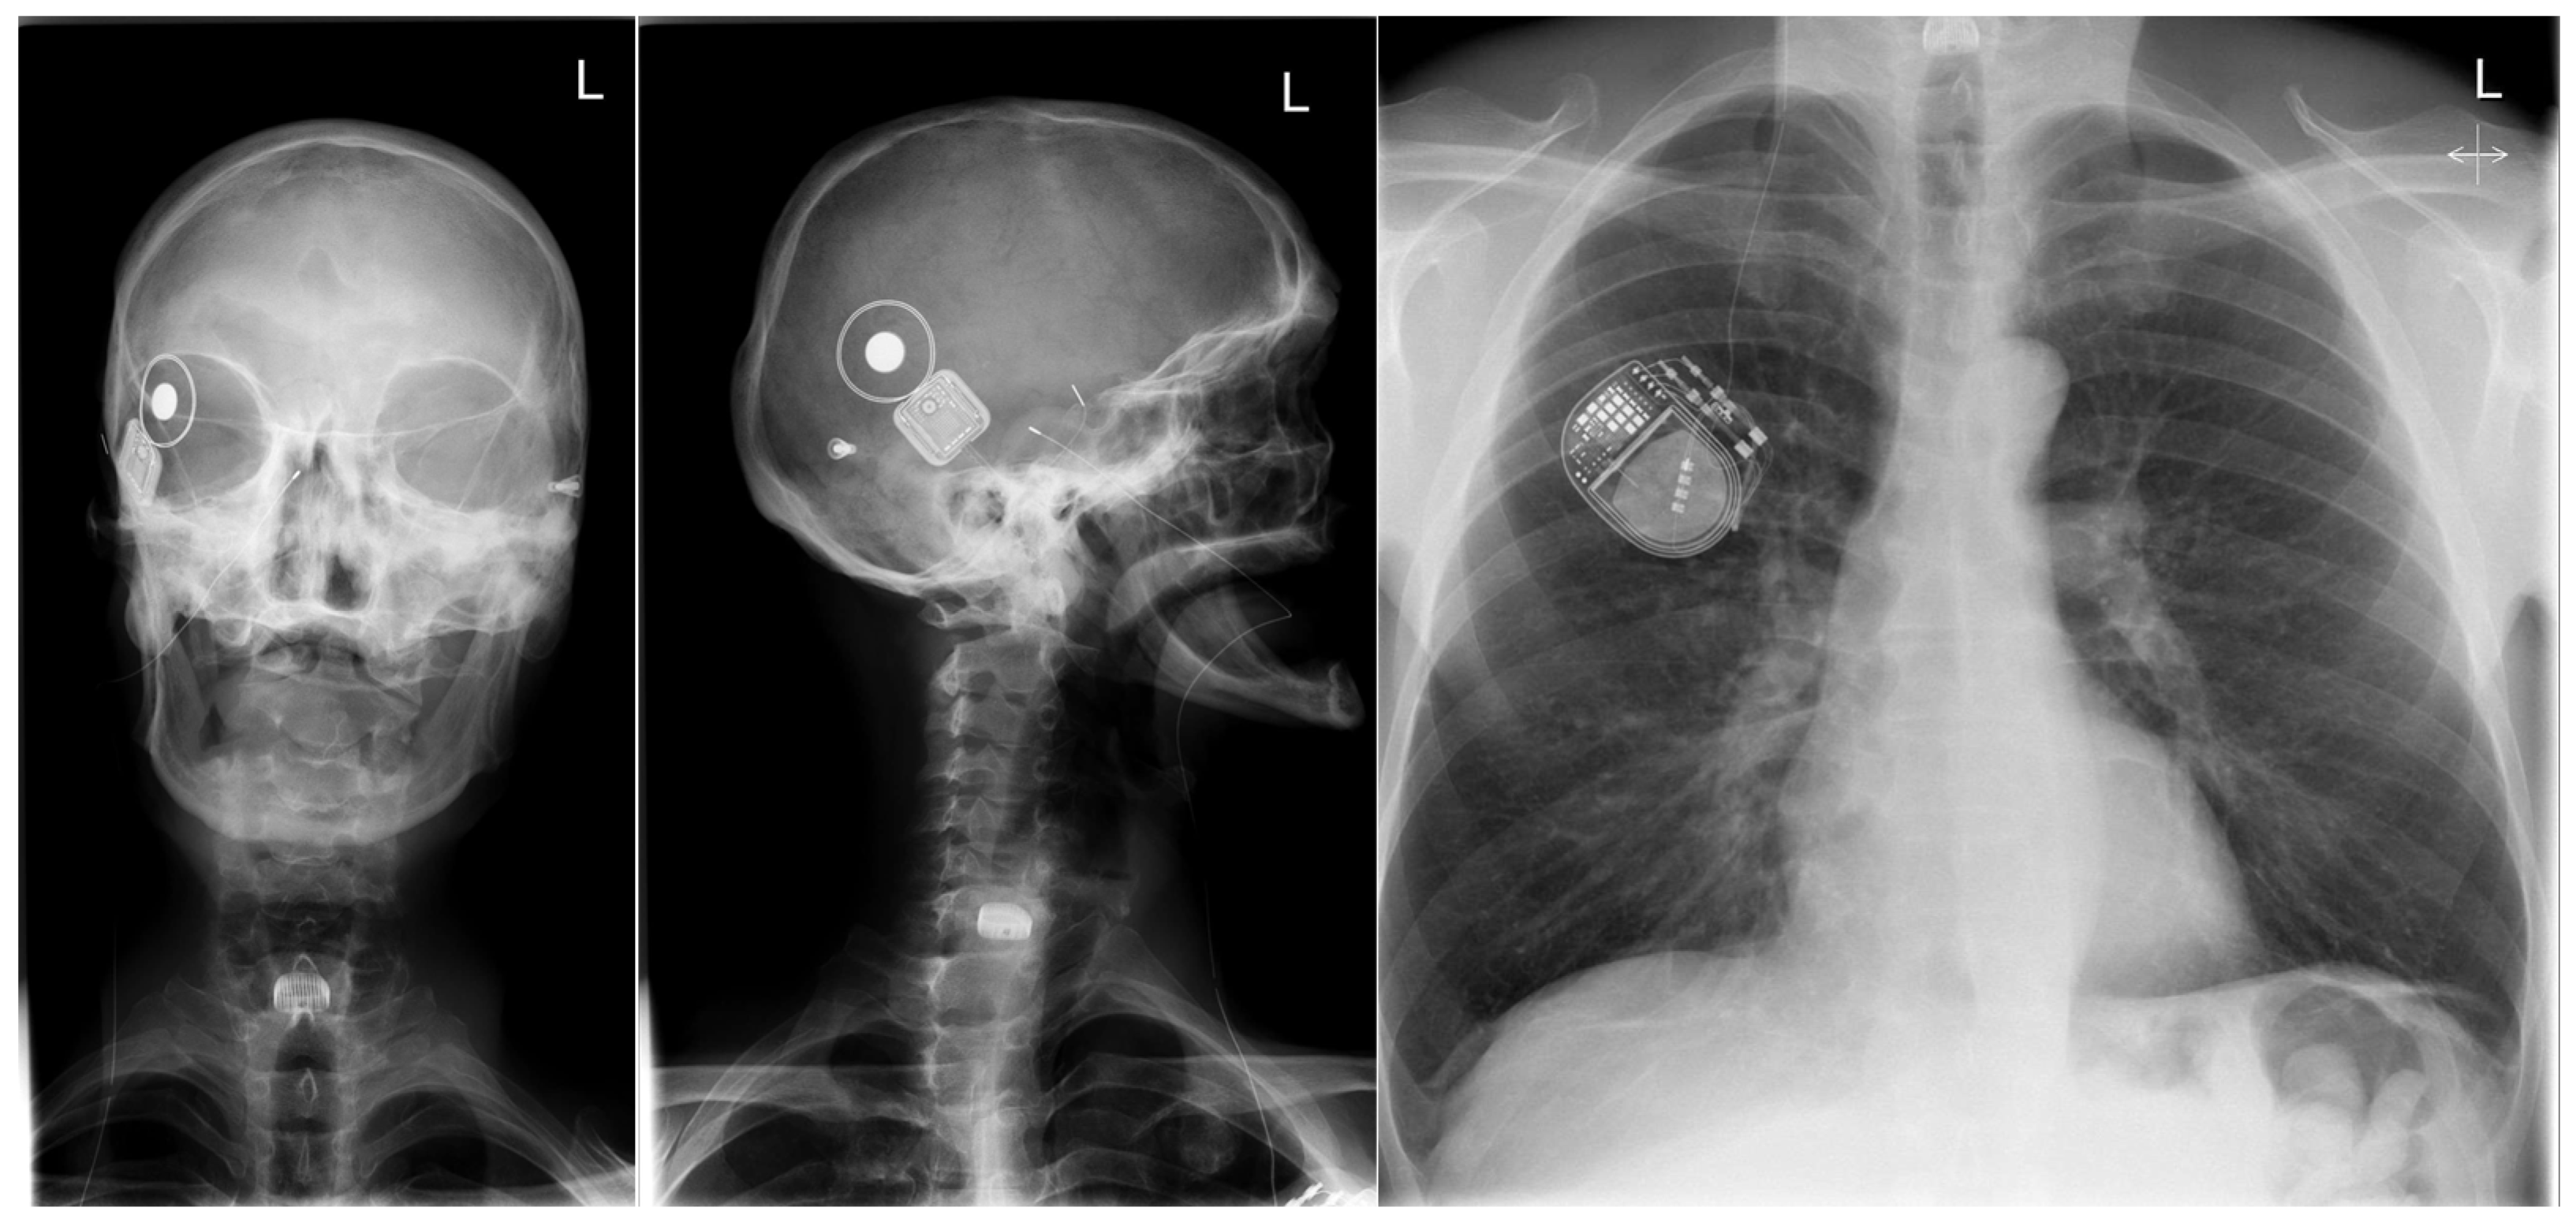

2. Case Presentation